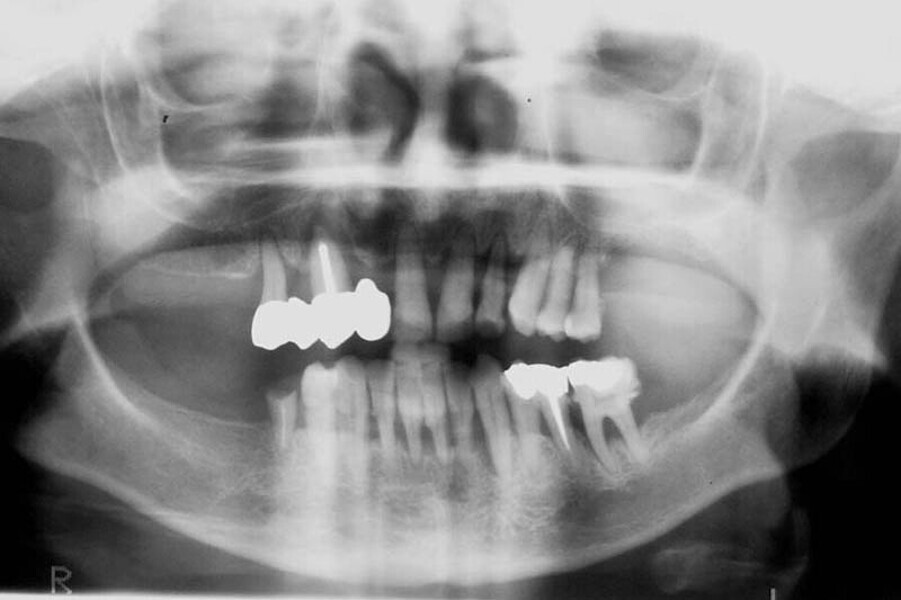

Fig. 24. Rx Pre-operatoria, Prótesis híbrida inmediata con 8 años de evolución y Rx Control a los 8 años.

Fig. 25. Rx Pre-operatoria, Prótesis híbrida inmediata con 8 años de evolución y Rx Control a los 8 años.

Fig. 26. Rx Pre-operatoria, Prótesis híbrida inmediata con 8 años de evolución y Rx Control a los 8 años.